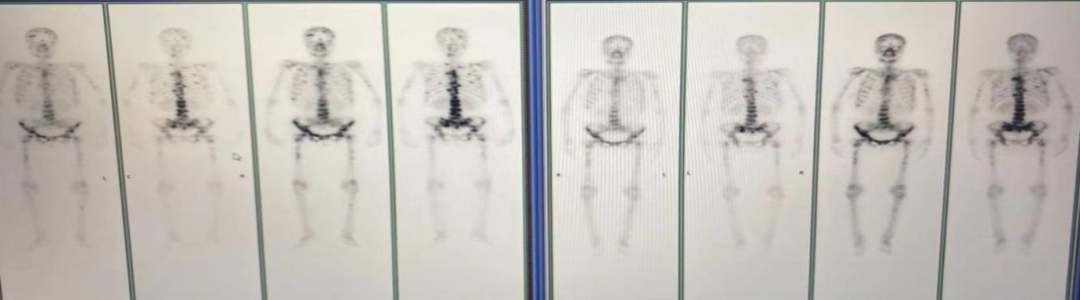

图4.肺窗

2021年4月7日双肺示:转移可能。